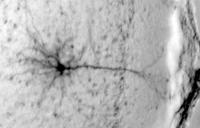

Black and white eye scan with branching dark lines.

The most striking changes the researchers saw appeared in neurons within the mouse equivalent of the human prefrontal cortex (PFC), which is involved in planning actions by suppressing inappropriate responses and maintaining working memory and attention. The area does not completely mature in people until their 20s.

In the binge drinking mice, certain PFC neurons were less able to generate persistent activity, and these changes appear to impair working memory. This finding is consistent with imaging studies that show decreased resting activity in the PFC of alcoholics and binge drinkers.